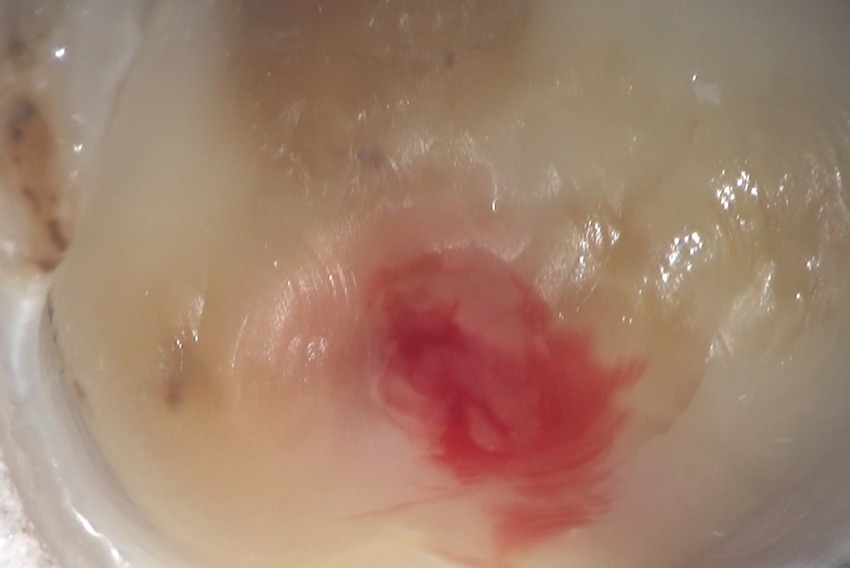

これが、虫歯になっている歯の最初の状況。